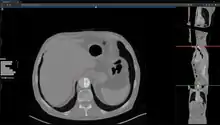

Studierfenster[1][2] is a free, non-commercial Open Science client/server-based Medical Imaging Processing (MIP) online framework. It offers capabilities, like viewing medical data (Computed Tomography (CT), Magnetic Resonance Imaging (MRI), etc.) in two-dimensional (2D) and three-dimensional space (3D) directly in a standard web browser, like Google Chrome, Mozilla Firefox, Safari or Microsoft Edge. Other functionalities are the calculation of Medical Metrics (Dice Score[3] and Hausdorff distance[4]), manual slice-by-slice outlining of structures in medical images (segmentation[5][6]), manual placing of (anatomical) landmarks in medical image data, viewing medical data in Virtual Reality (VR) and a facial reconstruction and registration of medical data for Augmented Reality (AR).[7]

Other features of Studierfenster are the automatic Cranial Implant Design with a neural network,[8][9] the inpainting of Aortic Dissections[10] with a Generative Adversarial Network(GAN)[11][12] and an automatic aortic landmark detection with Deep Learning[13] in Computed Tomography Angiography (CTA) scans.